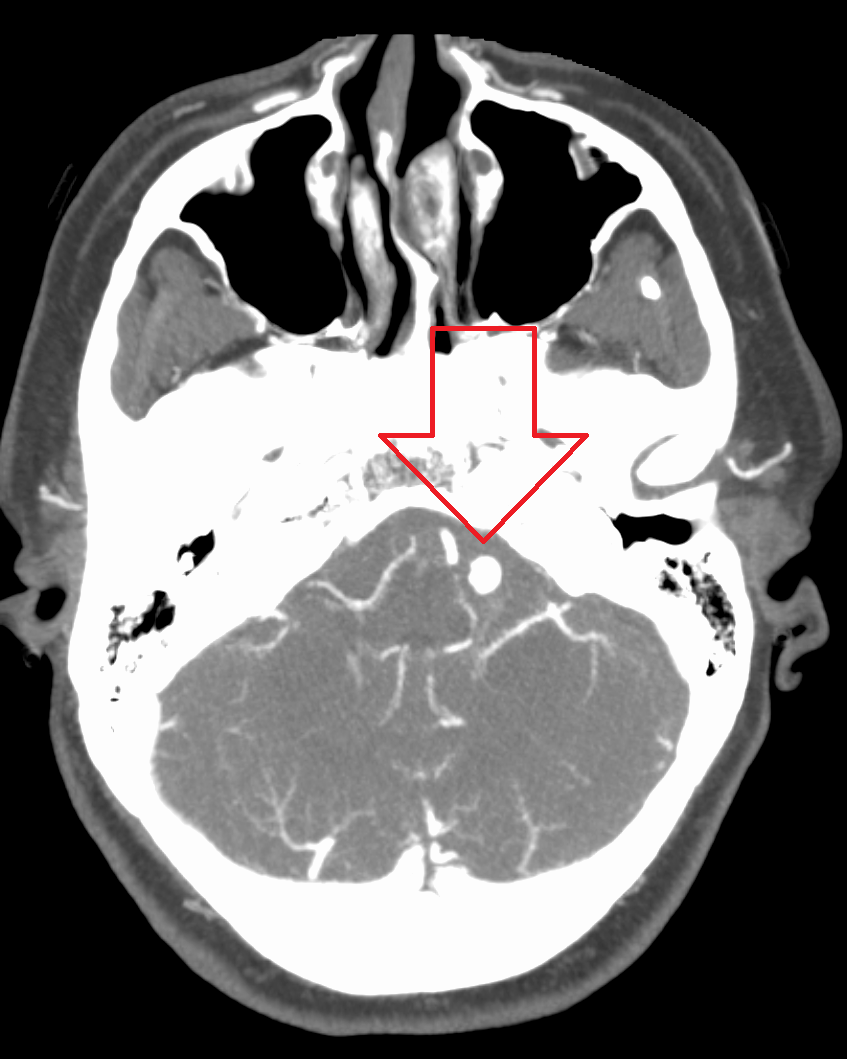

파열된 뇌동맥류는 일반적으로 컴퓨터 단층촬영(CT) 검사에서 지주막하 출혈 징후를 발견하여 진단한다. CT 검사 결과가 음성이지만 임상 소견상 파열된 동맥류가 의심되는 경우, 뇌척수액에서 혈액을 검출하기 위해 요추천자를 시행할 수 있다. 컴퓨터 단층촬영 혈관조영술(CTA)은 기존 혈관조영술의 대안이며, 동맥 카테터 삽입 없이 시행할 수 있다. 이 검사는 정기적인 CT 검사와 정맥에 주입된 조영제를 결합한 것이다. 조영제가 정맥에 주입되면 뇌동맥으로 이동하고, CT 검사를 사용하여 영상을 생성한다. 이러한 영상은 혈액이 뇌 동맥으로 어떻게 흐르는지 정확하게 보여준다.[39] CT 및 MRA도 유용하다.